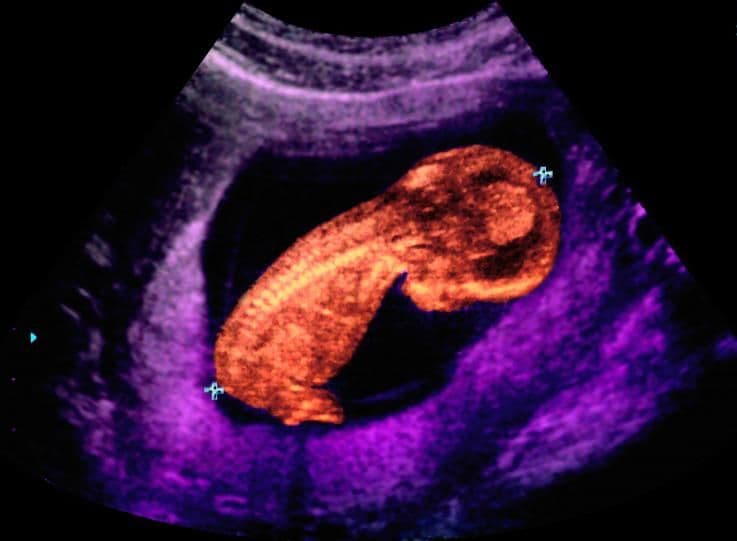

In this artificially coloured ultrasound scan of the baby within the uterus, the spine shows up especially clearly. The two blue crosses, at the top of the baby’s head and at his bottom, indicate where the crown to rump measurement is taken.